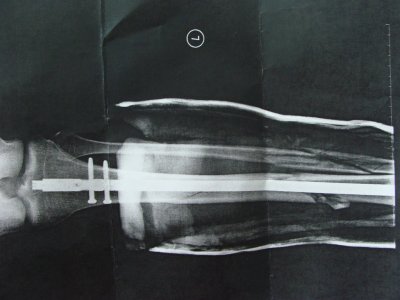

Всё последующеие два месяца я и провёл в этом ботинке. Его можно было снимать и одевать, для того чтобы мыть ногу. Периодически меня вызывали врачи на визит, делая рентген и наблюдая за процессом заживления костей. Где-то через полтора месяца мне разрешили применять один костыль для ходьбы (это скорее всего было их требование). Затем через две недели вообще без костылей. Прошло две недели, как я проходил без костылей, после обследования они мне разрешили ходить в обычной обуви, всмысле без того гипсозаменяющего приспособления.Вот уже почти две недели хожу без костылей и в нормальной обуви. Врачи хотели мне назначить терапию, но в связи с моим переездом, я не смог пойти на эти процедуры. Хотя врач сказал, что ничего и страшного. Вот снимок с последнего визита к врачу, 10 недель спустя после перелома:

DSC08661.JPG

DSC08663.JPG

Вопрос по поводу малой берцовой кости: судя по снимку, я вижу, что кость не срослась как следует. спрашивал врача, он сказал, что потребуется ещё время для сростания. Боюсь, что может сростись неправильно или какие то осложнения быть. Хотя когда врач прощупывал, то никаких болей не чувствовал